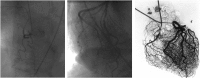

Far more extensive than the epicardial coronary vasculature that can be visualized angiographically is the coronary microcirculation, which foregoes routine imaging. Probably due to the lack of techniques able to provide tangible evidence of its crucial role, the clinical importance of coronary microvascular dysfunction is not fully appreciated. However, evidence gathered over the last several decades indicates that both functional and structural abnormalities of the coronary microvasculature can lead to myocardial ischaemia, often comparable with that caused by obstructive coronary artery disease. Indeed, a marked increase in coronary microvascular resistance can impair coronary blood flow and trigger angina pectoris, ischaemic ECG shifts, and myocardial perfusion defects, and lead to left ventricular dysfunction in patients who otherwise have patent epicardial coronary arteries. This condition--often referred to as 'chest pain with normal coronary arteries' or 'cardiac syndrome X'--encompasses several pathogenic mechanisms involving the coronary microcirculation. Of importance, coronary microvascular dysfunction can occur in conjunction with several other cardiac disease processes. In this article, we review the pathogenic mechanisms leading to coronary microvascular dysfunction and its diagnostic assessment, as well as the different clinical presentations and prognostic implications of microvascular angina. As such, this review aims to remove at least some of the mystery surrounding the notion of coronary microvascular dysfunction and to show why it represents a true clinical entity.